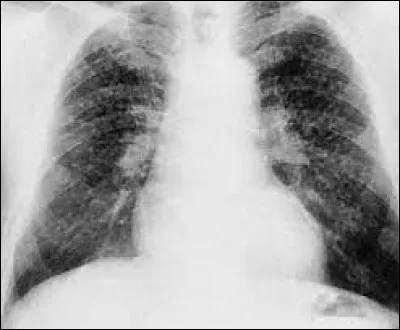

Quiz Classique Quiz Classique Quiz Charbon par Synapse58 Synapse58 313 joués - il y a 2 ans Culture générale autour du mot ''charbon'' ! QUIZ 15 QUESTIONS normal expert Question 1 / 15 Le charbon est de quelle origine ? VégétaleMinéraleAnimale difficile Question 2 / 15 Quel autre nom donne-t-on à la maladie du charbon ? Éréthisme charbonneuxArdeur charbonneuseFièvre charbonneuse difficile Question 3 / 15 Quel peintre néerlandais est l'auteur de ce tableau intitulé ''Mine de charbon dans le Borinage'' ? Gustav KlimtVincent Van GoghEdvard Munch Quizz.biz est un service gratuit financé principalement par la publicité. Pour nous soutenir et ne plus voir ce message : J'autorise les Annonces ou Je deviens Membre Plus facile Question 4 / 15 Quel est le nom de cette technique de dessin qui utilise comme crayons des bâtonnets de charbon de bois ? La temperaLe lavisLe fusain normal Question 5 / 15 Quelle maladie pulmonaire provoquée par l’inhalation de fines particules de charbon est appelée la maladie du mineur ? La sténoseLa fibroseLa silicose facile Question 6 / 15 Quelle est l'expression qui signifie qu'on est très impatient, qu'on attend une nouvelle ou un événement important avec anxiété ? Être sur des charbons flambantsÊtre sur des charbons brûlantsÊtre sur des charbons ardents normal Question 7 / 15 Quel est le nom des fragments de bois ou de charbon incomplètement brûlés qui s'échappent d'un foyer ? EscarbillesEscarcellesEscargoules facile Question 8 / 15 Quelles sont les premières indications médicales du charbon végétal activé ? L'acné, le psoriasis et l'eczémaInconforts digestifs ou intoxications et empoisonnementsLes troubles de la miction, les fuites urinaires facile Question 9 / 15 Quel est le nom du gaz naturel qui se dégage des couches de charbon et des terrains encaissants ? Le grisbiLe grisouLe grison normal Question 10 / 15 Quel est le nom du personnage de fiction qui qui se bat pour l'amélioration des conditions de vie des mineurs de charbon dans le roman ''Germinal'' d’Émile Zola ? RasseneurToussaint MaheuÉtienne Lantier normal Question 11 / 15 Quel agent est responsable du charbon du maïs (maladie du maïs) ? Un insecteUn champignonUne bactérie normal Question 12 / 15 Quelle est la bonne traduction du mot charbon en espagnol ? CarboneCarbónCarvão normal Question 13 / 15 ''Le Café Charbon'' est un établissement culturel, situé dans quel département, sachant que le chef-lieu de ce département est Nevers ? Le CherL'YonneLa Nièvre Quizz.biz est un service gratuit financé principalement par la publicité. Pour nous soutenir et ne plus voir ce message : J'autorise les Annonces ou Je deviens Membre Plus difficile Question 14 / 15 Quel animaux étaient utilisés pour donner l'alarme quand les émanations de monoxyde de carbone se faisaient menaçantes dans les mines de charbon ? Les canarisLes chiensLes souris difficile Question 15 / 15 Qui est l'auteur de cette citation : ''Il y a détournement de mineurs lorsqu'on préfère les inscrire au chômage plutôt que de les envoyer au charbon.'' ? Professeur ChoronFrancis BlanchePhilippe Bouvard Découvrir l'indice Une erreur dans ce Quiz ? Contactez l'auteur Justice Synapse58 181 joués - 23 heures Marcel & Marcelle Synapse58 245 joués - hier Culture générale ''Pluie'' ! Synapse58 3 858 joués - 3 jours Foin Synapse58 648 joués - 4 jours Algérie Synapse58 160 joués - 5 jours Sergent Synapse58 213 joués - 6 jours Culture générale ''nue'' Synapse58 315 joués - 7 jours Lundi Synapse58 2 533 joués - 8 jours Dindon, dinde Synapse58 384 joués - 9 jours Allez, du 'ballet' ! Synapse58 3 083 joués - 10 jours Et ''pie'' c'est tout ! Synapse58 2 685 joués - 11 jours Crime Synapse58 3 297 joués - 12 jours Vipère Synapse58 3 187 joués - 13 jours Clé, clef Synapse58 1 727 joués - 14 jours Capitaine Synapse58 337 joués - 15 jours